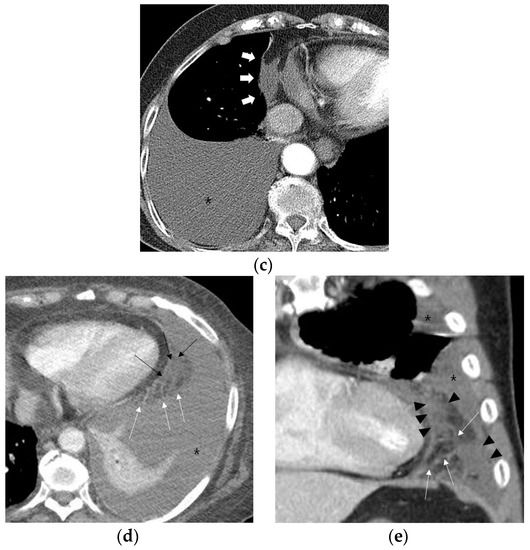

Fat attenuation with thin vessels can often be identified in the normal paracardiac area on chest CT (Figure 2a). Abnormal paracardiac fat stranding was defined as the presence of asymmetrical linear densities on the side ipsilateral to the pleural effusion, unaccompanied by tapering and branching ends, which would be more typical of normal paracardiac small vessels (Figure 2b). A paracardiac fluid collection was defined as an area of >1 cm2 with fluid attenuation (Hounsfield Unit = 0–30 on precontrast CT) (Figure 2c). An arbitrary low threshold valve of 1 cm2 was selected to avoid confusion between a subtle FC and prominent linear densities such as thick FS. Phlegmonous appearance in paracardiac fat was defined as the simultaneous presence of multifocal FS interspersed with multifocal FC in the paracardiac area (Figure 2d,e). We used the term “phlegmonous appearance” in paracardiac fat in this study due to the similarity in the CT findings of periappendiceal phlegmon in patients with appendicitis [9]. An enlarged paracardiac lymph node was considered to be present for lymph node >1 cm in short axis diameter. With respect to tuberculous immune response, we hypothesized that the extent of paracardiac fat stranding and fluid collection in the ipsilateral paracardiac fat might have a positive correlation with the strength of the immune response or inflammation within the pleural effusion. To evaluate such a relationship in pleural TB patients, we investigated whether there is a correlation between the level of pleural ADA value and serum CRP value, and the prevalence of phlegmonous appearance, or FS in the ipsilateral paracardiac fat in patients with pleural TB. Among 351 patients in pleural TB, 322 patients had available laboratory results for pleural fluid ADA level. In addition, 334 patients with pleural TB had an available blood CRP level.

Figure 2.

Representative cases demonstrating normal appearance, fat stranding, fluid collection, and phlegmonous appearance in the ipsilateral paracardiac fat on chest computed tomography. (a) Normal appearance of paracardiac fat on a coronal CT image at the level of left ventricle. Note a lack of fat stranding or a fluid collection in the paracardiac fat of a patient with pleural tuberculosis (white arrows). (b) A case of right pleural tuberculosis (asterisks) in a 67-year-old female with fat stranding (black and white arrows) in the right paracardiac fat on an axial CT image at the level of the right ventricle. (c) A case of right pleural tuberculosis (asterisk) in a 77-year-old female demonstrating a fluid collection (white arrows) in the right paracardiac fat on an axial CT image at the level of the left ventricle. (d,e) Two cases of left pleural tuberculosis (asterisk) with a phlegmon-like appearance in left paracardiac fat in a 74-year-old female on axial CT image (d), and in a 58-year-old male on coronal CT (e) at the level of the left ventricle. Note multiple fat strands (white arrows) interspersed with multiple fluid collections (black arrows or black arrowheads) in the paracardiac fat ipsilateral to the left pleural effusion.